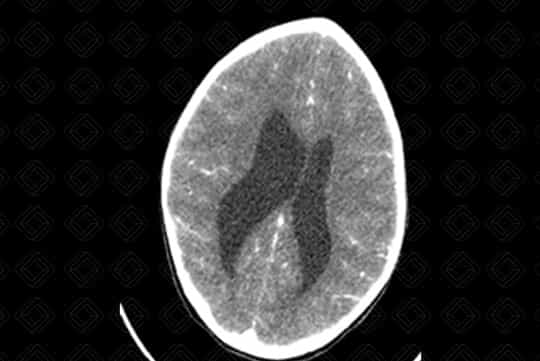

Texto alternativo para a imagem Figura 1. Créditos: Dra. Elazir Mota - Rio de Janeiro/RJ

Descrição das figuras 1, 2, 3, 4 e 5: Tomografia computadorizada do crânio após administração do contraste venoso nas reformatações axial e coronal. Paciente de 4 anos com lesão discretamente captante de contraste (asterisco - figura 2) no corno anterior do ventrículo lateral direito, causando obstrução do forame de Monro e hidrocefalia secundária, de etiologia obstrutiva. [cms-watermark]